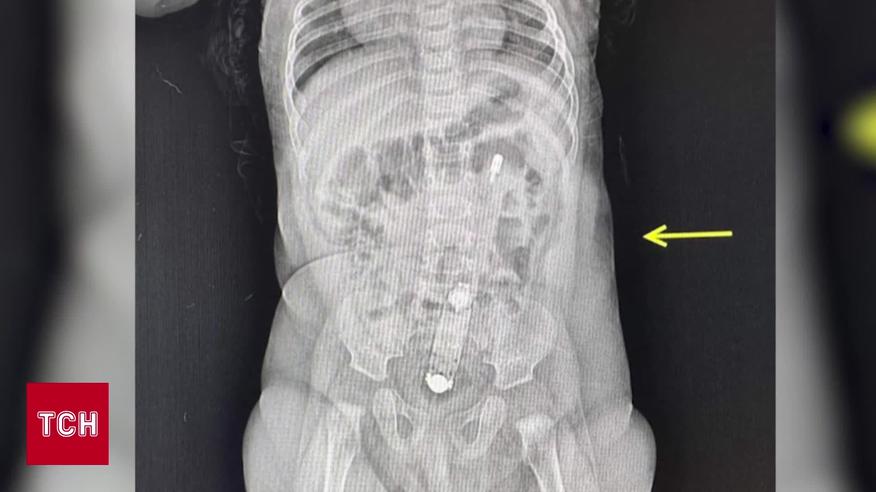

В Луцке медики доставали термометр из кишечника полугодовалой девочки. В больницу к медикам обратилась мать младенца. Объяснила: у ребенка был запор, воспользоваться термометром ему, вроде бы, посоветовали в Сети. Медики поначалу не поверили, но впоследствии увидели термометр на рентгене. И ребенка все-таки пришлось оперировать. Как она себя чувствует – смотрите в сюжете журналистки ТСН Татьяны Хомич.